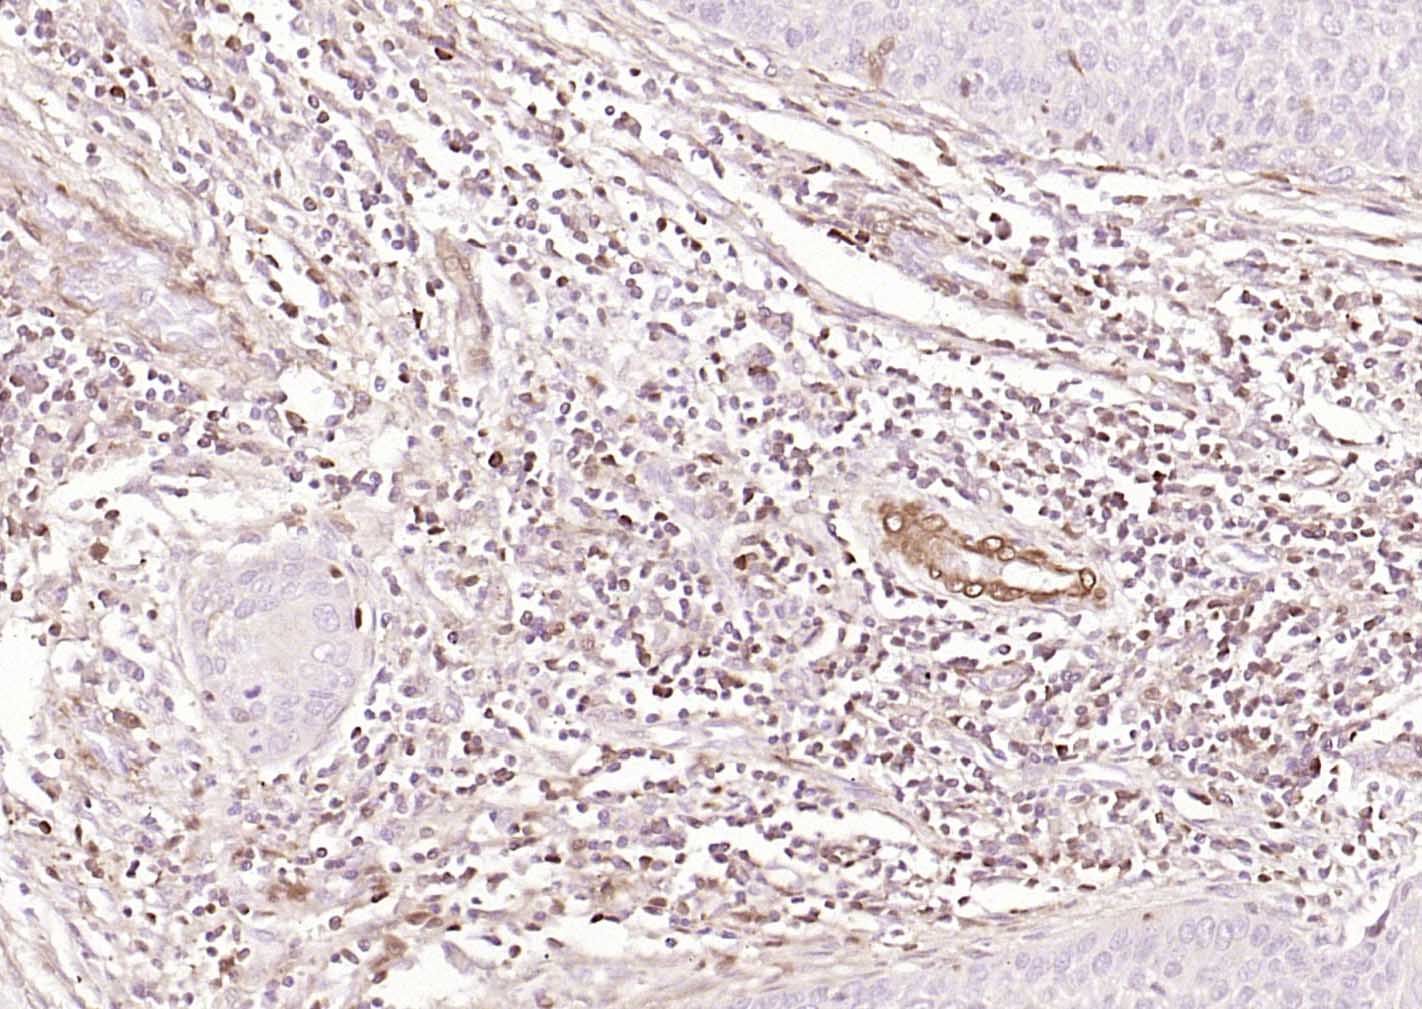

Paraformaldehyde-fixed, paraffin embedded (human cervical carcinoma); Antigen retrieval by boiling in sodium citrate buffer (pH6.0) for 15min; Block endogenous peroxidase by 3% hydrogen peroxide for 20 minutes; Blocking buffer (normal goat serum) at 37°C for 30min; Incubation with (S100A4) Monoclonal Antibody, Unconjugated (bsm-60916M) at 1:100 overnight at 4°C, followed by operating according to SP Kit(Mouse)(sp-0024)instructionsand DAB staining.